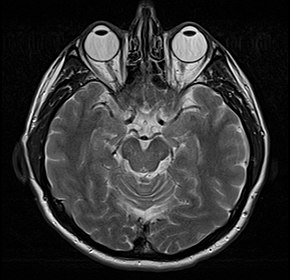

Противопоказания к МРТ

Магнитно-резонансная томография — это безопасное обследование без лучевой нагрузки, но и она имеет ряд противопоказаний в зависимости от модели томографа и протокола обследования — с контрастом или без. Томография нашла широкое применение в нейрохирургической, онкологической, ортопедической и неврологической практике для исследования позвоночника, головного мозга, сосудов, суставов, внутренних органов и мягких тканей.